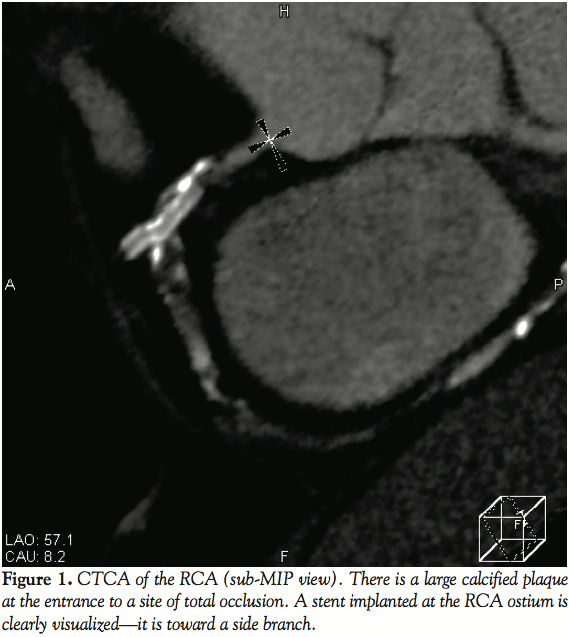

Case report. A 55-year-old male with hypertension and diabetes was hospitalized with poorly controlled typical angina pectoris in July 2008. He had a history of PCI in the right coronary artery (RCA) and coronary artery bypass grafting in 1998 when the left internal thoracic artery had been anastomosed to the obtuse marginal at another hospital. CTCA was performed with a 64-slice CT scanner (Aquilion 64, Toshiba). Scans obtained in the sub-MIP view showed a large calcified plaque at the entrance to a total occlusion of the RCA (Figure 1). The length of the CTO was about 20 mm. A stent implanted at the RCA ostium 10 years previously was also well visualized. It seemed to be misdirected toward a side branch, and the proximal part of the stent was seen to be located in a false lumen on short axis views of the RCA (Figure 2).

Problems that arise with the retrograde approach include difficulty in advancing the guidewire through the collateral channel, as well as subsequently crossing the CTO with the guidewire and devices. In the patient reported here, the stent previously implanted at the RCA ostium was angled toward a side branch on pre-procedural CTCA. Although the stent proximal to the mid segment of the CTO seemed to be inside the true lumen on the normal MIP view, the mid-to-distal part of the stent was found to be in a false lumen on the short axis view. Thus, the information obtained by pre-procedural CTCA was useful for deciding the therapeutic strategy. We predicted that a guidewire would not be able to enter the true lumen via the antegrade approach based on the CTCA findings, so we employed the retrograde approach via a septal collateral. Because the stent was implanted in a false lumen, we performed balloon dilatation of the subintimal space and stent struts and succeeded in advancing the guidewire by the CART technique after failure of the kissing wire technique and knuckle wire technique.